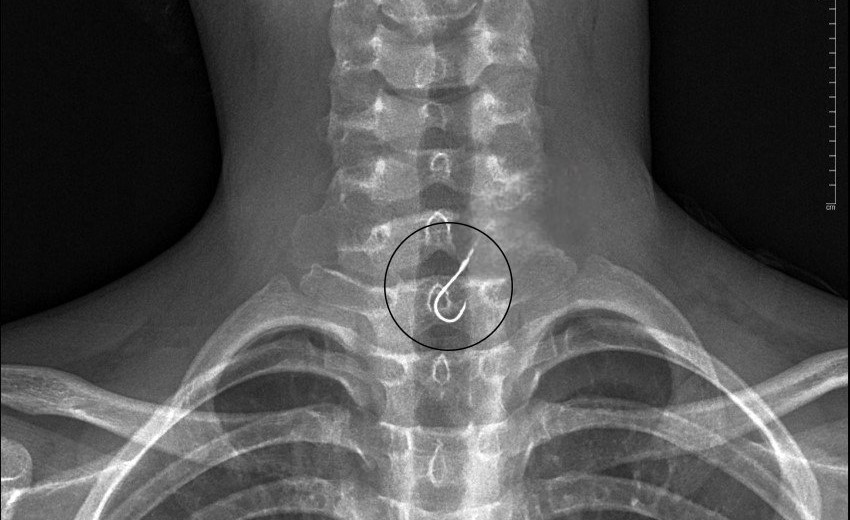

| Phim X-quang cho thấy, lưỡi câu nằm trong thực quản của bệnh nhân. |

Gia đình đưa em vào Bệnh viện Bà Rịa để cấp cứu. Tại đây, bác sĩ đã thăm khám và chụp X-quang cho bệnh nhân, tiến hành hội chẩn với bác sĩ nội soi và gây mê. Sau đó, em K. được thực hiện nội soi thực quản gắp dị vật. Khi nội soi vào thực quản cho thấy, lưỡi câu có dính theo sợi dây và đang bị kẹt ở thực quản. Bác sĩ nội soi đã gắp lưỡi câu ra ngoài an toàn, niêm mạc vùng hầu họng và thực quản của bệnh nhân không bị tổn thương.